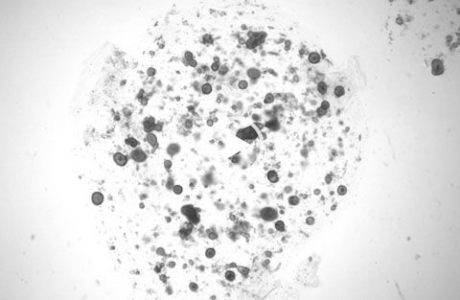

Ученые использовали технологию органоидов, чтобы вырастить в миниатюрные версии слезной железы мыши и человека. По сути, органоиды —крошечные трехмерные структуры, имитирующие функции настоящих органов. Результаты опубликованы в журнале Cell Stem Cell, информируют Экономические новости.

Подобно тому, как люди плачут в ответ, например, на боль, органоиды плачут в ответ на химические раздражители, такие как норадреналин. Клетки органоидов проливают слезы на внутренней части органоида, который называется просветом. В результате органоид раздувается, как воздушный шар. Таким образом, и размер можно использовать как индикатор слезоотделения и секреции. Дальнейшие эксперименты показали, что разные клетки слезной железы производят разные компоненты слезы. И эти клетки по-разному реагируют на стимулы, вызывающие слезу.